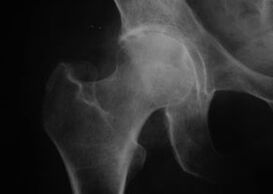

- Cxatthrosis,

Coxatiosis, arthrosis ti awọn ibap apapọ

Pẹlu aisan yii, aworan ile-iwosan Ayebaye kan ti a ṣe akiyesi arthrosis.

Ami akọkọ ti coxatthrosis jẹ ibanujẹ ninu apapọ ibadi lẹhin iṣẹ ṣiṣe.

Pẹlu ifa ilọsiwaju ti onitẹsiwaju, irora pọ, lile ati ilopo lopin han.

Awọn alaisan ti o ni ọna lile ti idalẹnu iṣelọpọ ti o kan ṣe idiwọ ọwọ, yago fun gbigbe si ori rẹ, ati lakoko ti o wa ni adaduro, yan awọn ipo ninu eyiti a lero irora naa kere ju.